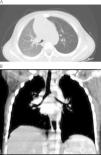

A la exploración física presentaba estertores crepitantes en base pulmonar izquierda sin otros hallazgos patológicos. Se realizaron hemograma, bioquímica, gasometría venosa e IgE, que fueron normales. PPD negativo. La función pulmonar estudiada mediante análisis de asa flujo-volumen a respiración corriente (porcentaje de tiempo espiratorio hasta el pico flujo [Tptef/Te=24,7%] y morfología) fue normal. Así mismo, la fracción exhalada de óxido nítrico (FENO), medida on-line a respiraciones múltiples, también fue normal (7,5ppb a flujo de 200ml/s; coeficiente de variabilidad 10%). La radiografía de tórax mostraba una atelectasia retrocardiaca e hiperinsuflación discreta del hemitórax izquierdo y en el TC pulmonar de alta resolución se objetivó una estenosis de bronquio principal izquierdo en toda su extensión con pulmón izquierdo hiperlucente (fig. 1). Se realizó fibrobroncoscopia flexible que confirmó la presencia de una neoformación con base posteriomedial pediculada, lisa y muy vascularizada en tercio proximal de bronquio principal izquierdo con oclusión del 90% de la luz bronquial. Posteriormente, se realizó resección completa de la masa endobronquial mediante broncoscopio rígido y aplicación de mitomicina C tópica (fig. 2). El estudio anatomopatológico de la masa confirmó el diagnóstico de hamartoma condromesenquimal endobronquial (fig. 3). Actualmente, tras un periodo de seguimiento de 12 meses desde la resección del tumor, la paciente ha presentado una evolución favorable con resolución de la clínica y fibrobroncoscopias sucesivas sin tumor residual.